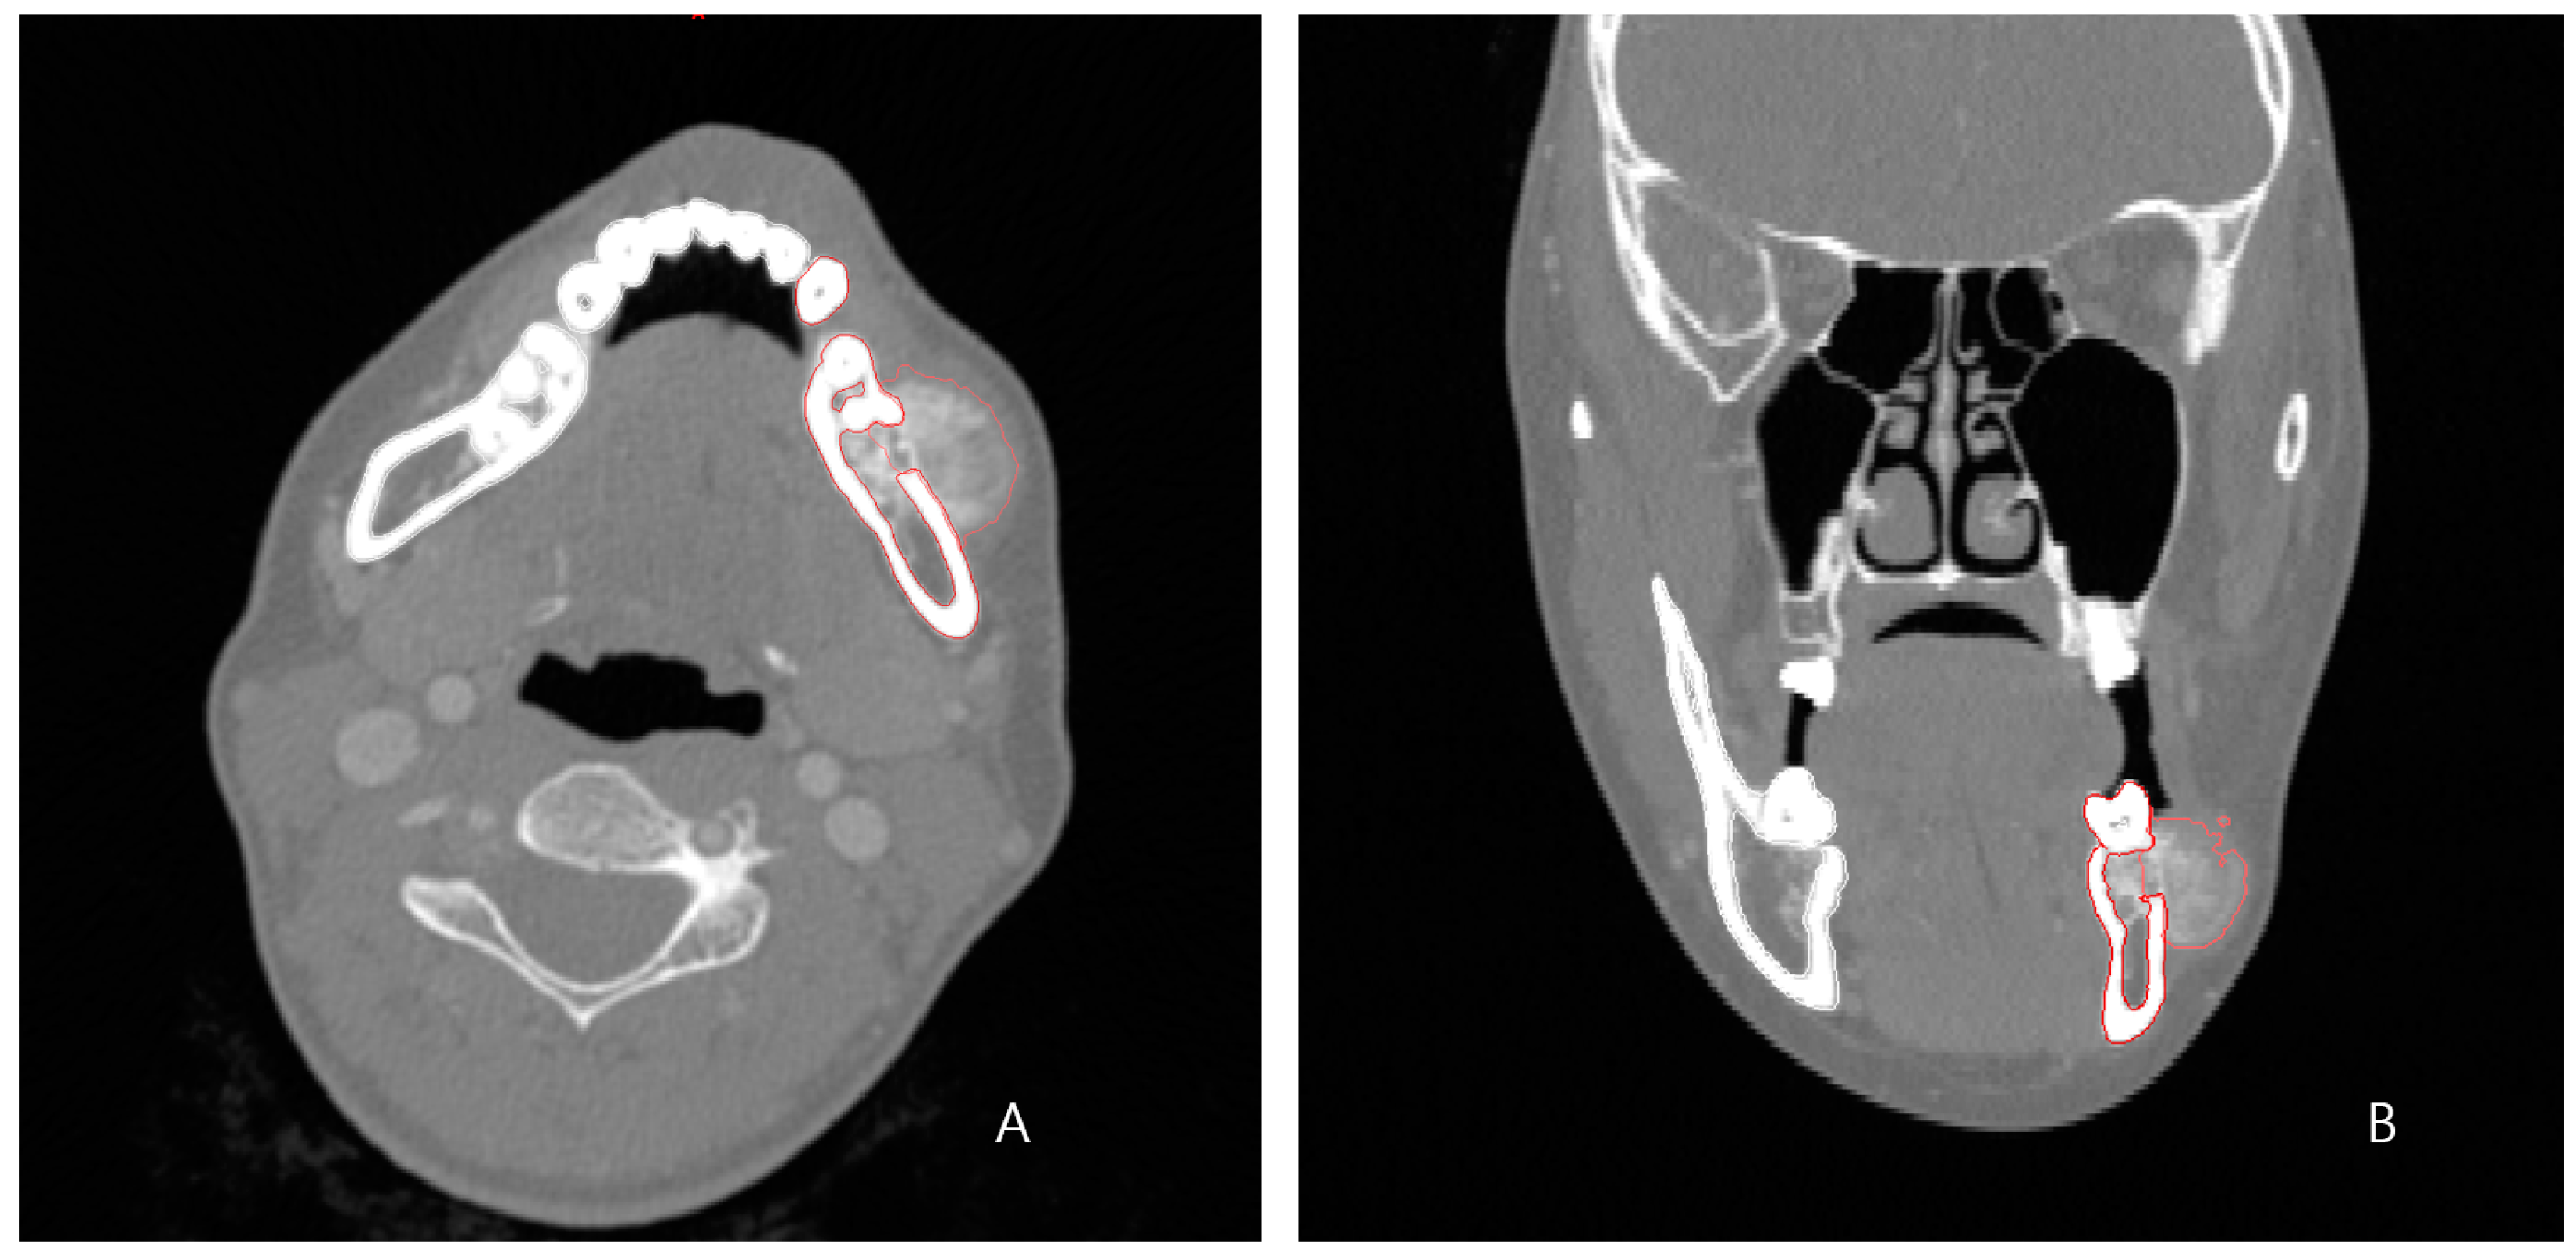

A 24-year-old female patient was identified with osteosarcoma of the left mandible body and referred to Kyung Hee University Dental Hospital. Preoperative enhanced computed tomography (CT) and enhanced magnetic resonance imaging (MRI) confirmed a tumor of approximately 2.5 cm that had eroded the buccal cortical bone and was bulging out (Figure 1). A wide excision, including segmental mandibulectomy, was planned with a sufficient safety margin. The fibula free flap was considered first since a bony free flap containing soft tissue was required to repair the lining oral mucosa and mandible.

Figure 1. Preoperative enhanced CT (1.0 mm slice) scan showing the malignant tumor eroded the left buccal cortical bone and bulged. (A) axial view; (B) frontal view (red lines outline the lesion and surrounding tissue).